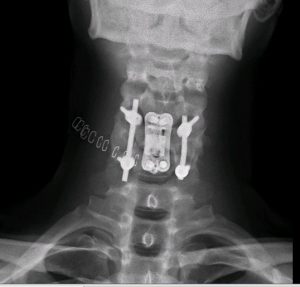

Accidente tráfico. Politrauma. Fractura cervical C5 inestable con compresión medular

Se realizó corpectomía C5 con reconstrucción anterior en un primer tiempo (prótesis expansible + placa cervical). En el mismo acto, se dio la vuelta al paciente y se realizó una fijación posterior para asegurar el montaje (dadas las lesiones ligamentosas asociadas).